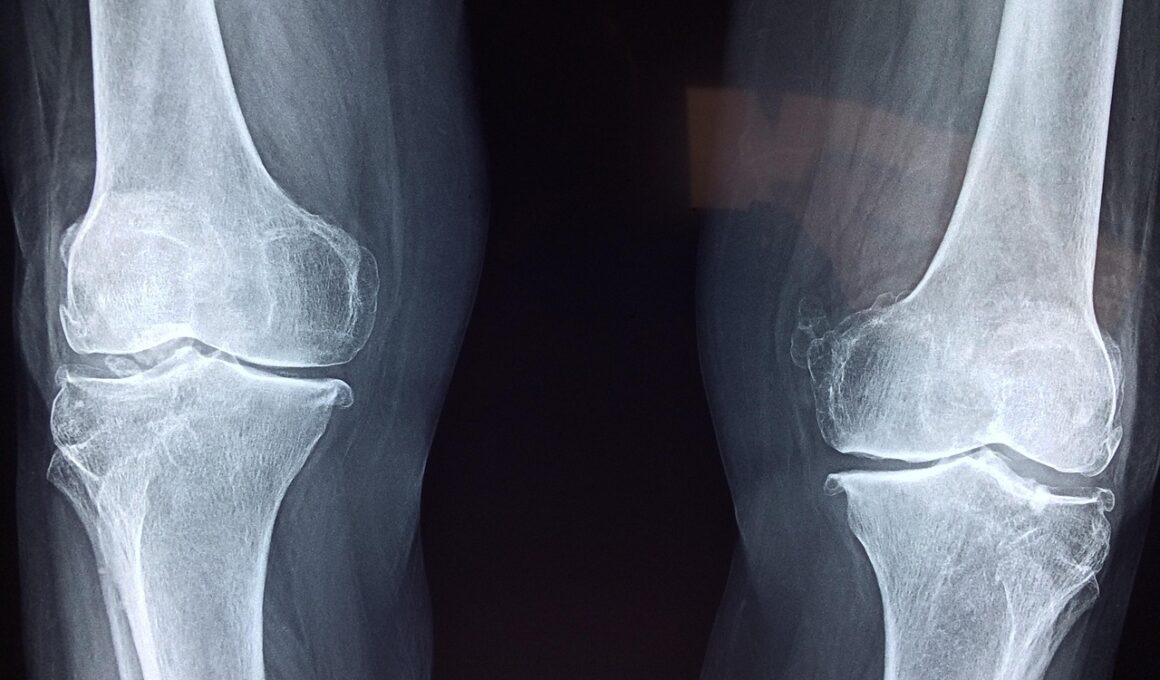

Investigating the physiological mechanics of joints unveils secrets about movement efficiency and adaptability. The mechanics of how joints operate involve not just the bones but also muscles, tendons, and ligaments. Each element plays a crucial role in facilitating smooth motion and ensuring joint stability. Take, for instance, the intricate structure of the human knee joint, where ligaments prevent excessive movement and stabilize the joint during complex movements. Gait analysis in humans exemplifies how understanding joint mechanics aids in addressing movement deficiencies and developing rehabilitation techniques. Similarly, in animals, understanding joint mechanics helps optimize their natural movements. By studying various species, researchers can explore how differences in joint mechanics affect speed, agility, and endurance. This knowledge is vital for sports medicine and improving athletic performance. For instance, it explains why some terrestrial mammals excel in sprinting while others are better adapted for endurance. As comparative anatomy evolves with technological advancements, the potential for new insights into joint mechanics and their applications expands considerably. Overall, understanding joint mechanics enhances our knowledge of mobility within the animal kingdom.

Clinical implications of joint study extend into veterinary medicine, biomechanics, and rehabilitation sciences. Understanding the anatomy and mechanics of joints is crucial for diagnosing and treating joint-related disorders in various species, including humans. Conditions such as osteoarthritis significantly affect joint function, necessitating advanced knowledge of joint structure for effective management strategies. Insights gained from comparative anatomy guide both clinical practices and surgical interventions. For instance, techniques developed for human joint replacements have roots in studies of joint anatomy across different animals. Moreover, the understanding of ligaments and cartilage health is vital in sports medicine, where joint injuries can impact performance. By examining joint adaptations among species, veterinarians and healthcare professionals can devise innovative treatments that enhance recovery. Furthermore, biomechanics research continuously informs us how various species utilize their joints efficiently in movement. This information can influence training regimens, prevent injuries, and improve performance in both human athletes and working animals. Therefore, a comprehensive grasp of joint anatomy is invaluable across a spectrum of disciplines, paving the way for advancements in healthcare and performance optimization.